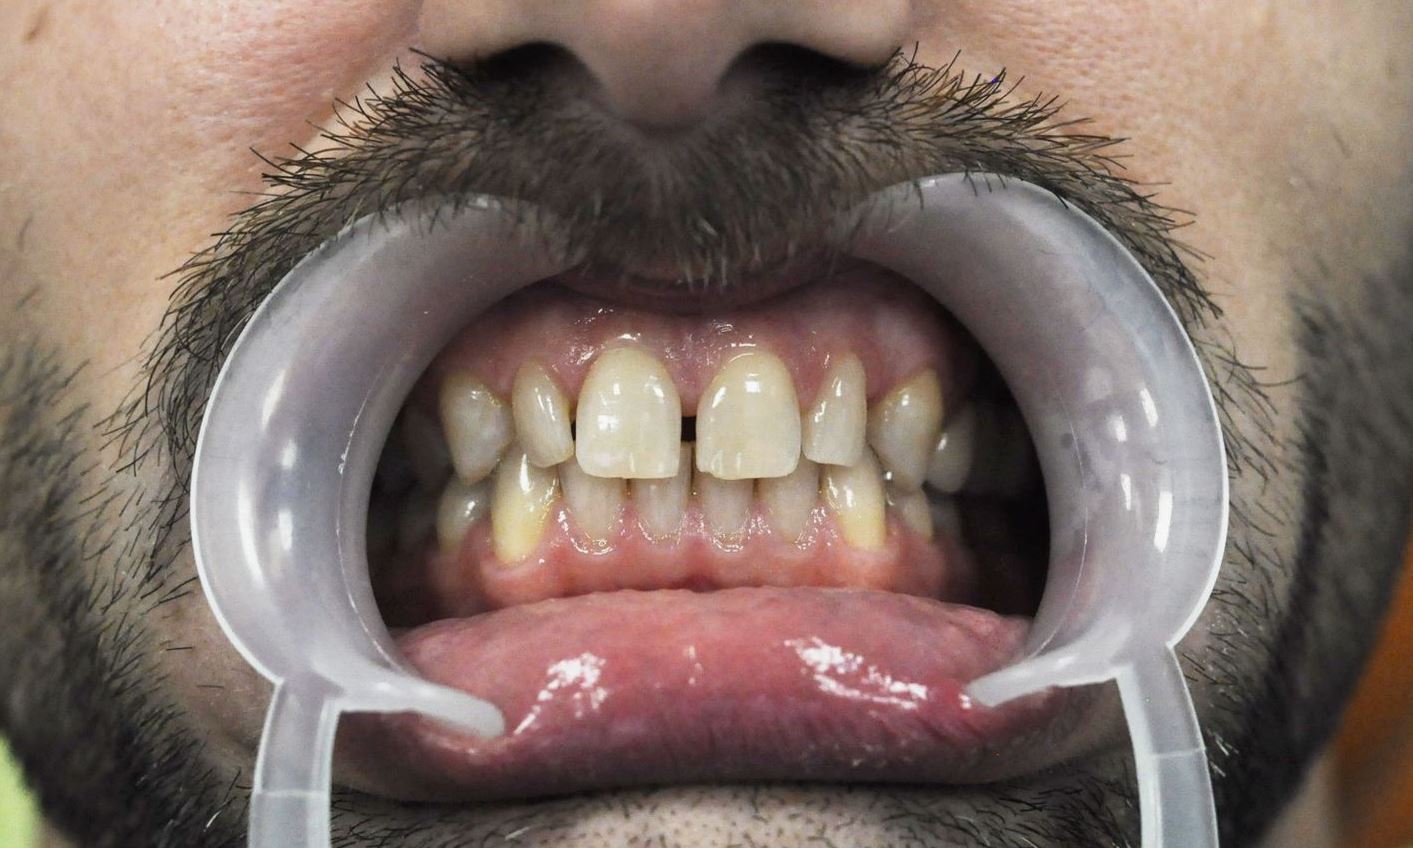

Przykłady prac protetycznych